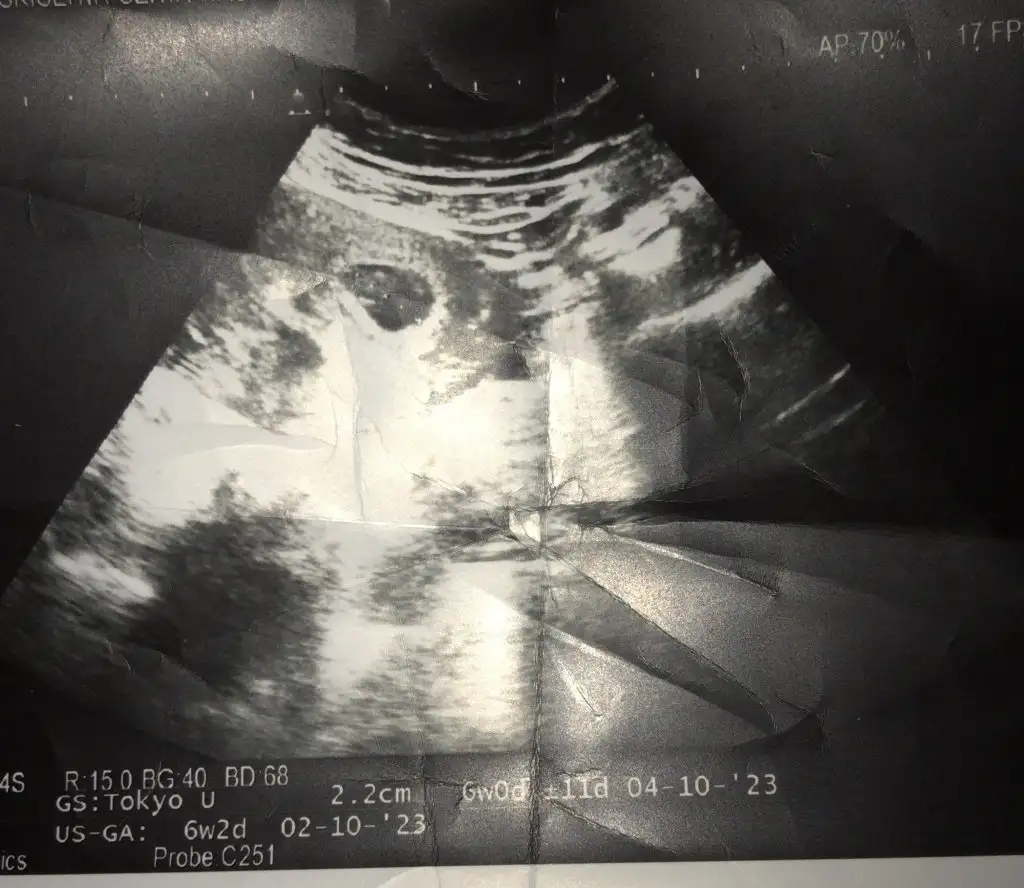

7+3 ve 6 haftalık görüntü tahmin yapar mısınız?